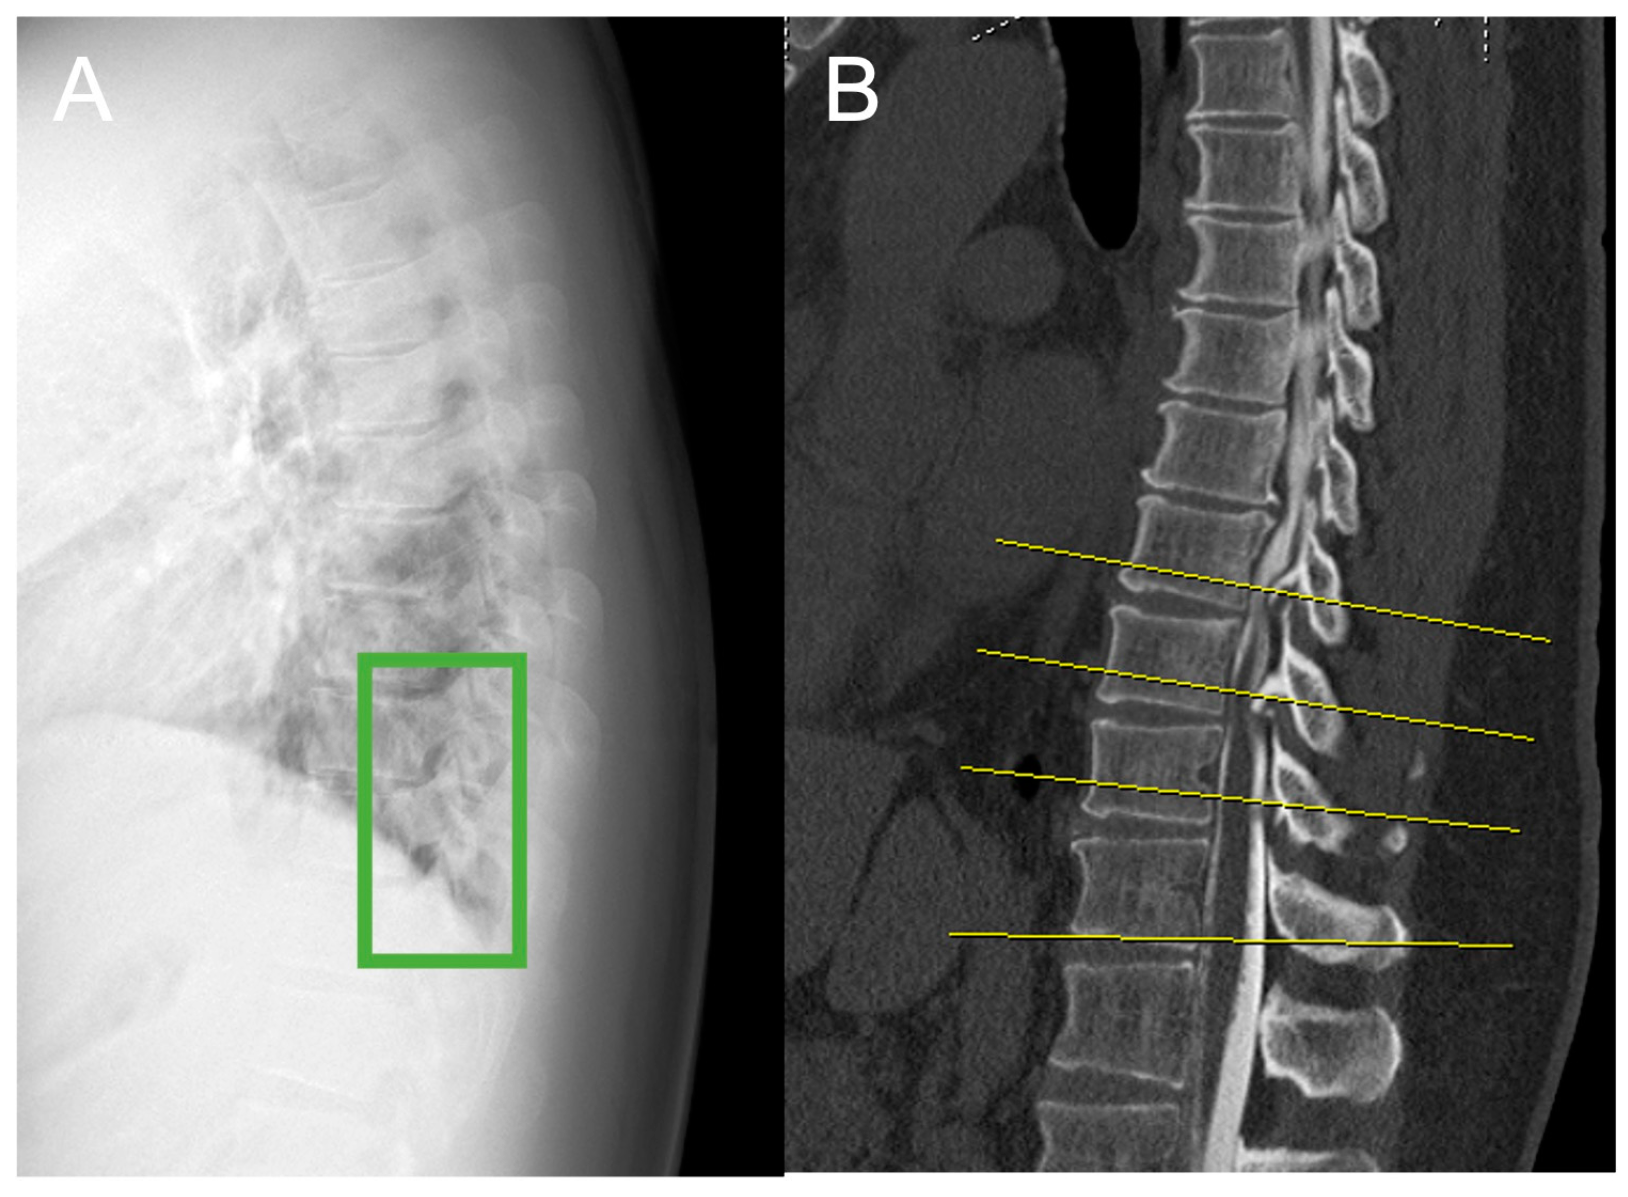

2.2. Plain Radiograph Dataset

2.3. Image Preparation and Annotation